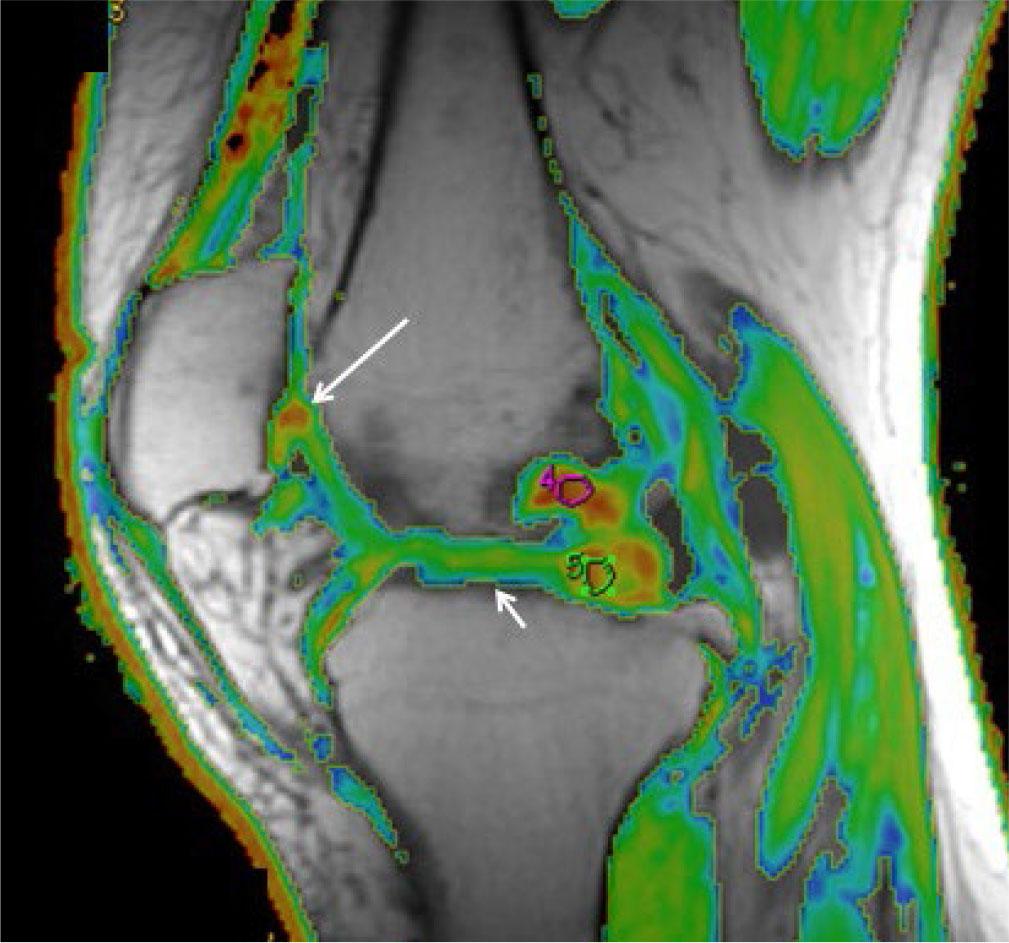

Techniques that analyze cartilage composition like T2-mapping, which assesses collagen and water content (Fig. 24), and delayed gadolinium-enhanced MRI of cartilage (dGEMRIC), which assesses glycosaminoglycan content, have been developed. These are being investigated for the early diagnosis of OA, monitoring treatment response, and possible intervention at an early reversible stage(25).

Fig. 24.

Cartilage imaging. Sagittal T2 mapping shows different color shades of the cartilage based on the diffusing fluid signal. Color shade towards red indicates cartilage damage(long arrow) and shade towards blue indicates healthy cartilage (small arrow)